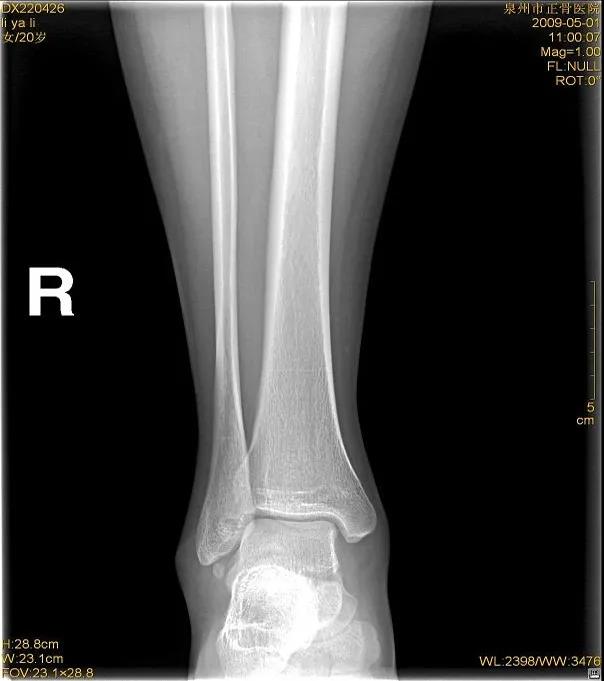

X线片:基本的辅助检查(应注意某些情况并非骨折)CT:能进一步检查隐匿性骨折或撕脱性骨折MRI:可检查肌腱、韧带的损伤肌骨超声:可代替或结合MRI检查软组织的损伤

X线

踝关节正位

踝关节侧位

虽然有所防备,但有时难免发生意外。这时,患者可以先自行评估是否出现关节畸形移位或形成假关节(骨头断裂)等,如果遇到这类严重情况应固定后立即就医,如果只是局部的肿胀瘀斑,疼痛程度较低,就可以先自我急救。伤者在进行急救处理后,如有条件最好在医院进行X线或CT检查,因为小骨头的断裂或撕裂等问题并不会引起强烈的疼痛或肿胀等,但如果没有有效的医疗支具固定可能会致骨折错位或损伤进一步加剧,后期恢复不充分,还会导致陈旧性软组织受伤,在关节尤其负重部位容易引发骨关节病等慢性疾病。